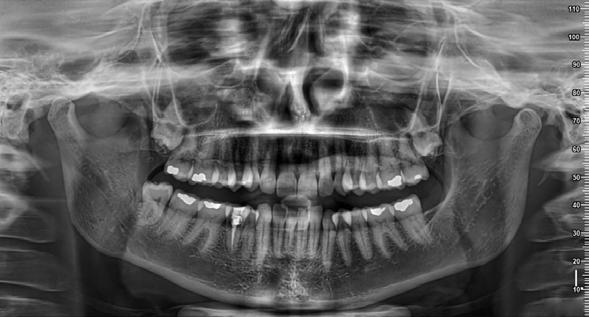

1. ábra: Kiindulási panorámaröntgen.

2. ábra: Kiindulási periapikális felvétel.

A radiológiai felvételek elemzése során a fog gyökércsúcsának megfelelően radiolucens elváltozást észleltünk, valamint a fognyak területének megfelelően szintén egy radiolucens területet figyelhettünk meg (1–2. ábra). Az elváltozások kiterjedésének és mélységének pontosabb meghatározása érdekében CBCT-felvétel készült (3. ábra). A felvétel alapján Heithersay-féle III. osztályú külső fognyaki gyökérfelszívódást diagnosztizáltunk (Heithersay Class III external cervical invasive root resorption; ECIR). Ezzel egyidejűleg pedig szimptomatikus periapikális periodontitis is fennállt. Ezt követően a pácienst a vizsgálati eredményekről, a kezelési alternatívákról és a várható prognózisról is tájékoztattuk.

3. a–d ábra: A koronális síkú metszeten jól megfigyelhető a lézió mesio-distalis kiterjedése (a), a szaggitális síkú metszet a lézió vesztibulo-orális nagyságát mutatja (b), a gyökércsúcs körül elhelyezkedő lézió a 3 dimenziós rekonstrukciós képen és a mesio-disztális irányú metszeten is jól megfigyelhető (c–d).

A cikkekben bemutatott esetnél a kezelésre szoruló fog gyökércsúcsánál periapikális lézió volt megfigyelhető és ezzel egyidejűleg külső fognyaki gyökérrezorpció is fennállt. A periapikális és a rezorptív lézió méretének pontos meghatározását és térbeli elhelyezkedésének vizsgálatát CBCT-felvétel segítségével végeztük.

1. ábra: Kiindulási röntgenfelvétel. – 2. a–c. ábra: A horizontális irányú metszeten kiterjedt csontpusztulás jelei láthatóak (a), a vertikális irányú metszeteken mindkét középső metszőfognak megfelelően észlelhető a csontpusztulás (b–c).